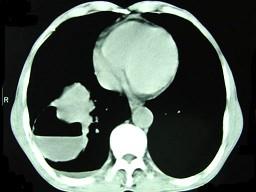

问题 男,76岁,胸痛伴咳嗽,咯血低热一月,CT检查如图,最可能的诊断为 ( )

选项 A、右下肺包虫病 B、右侧包裹性积液 C、右下肺癌伴空洞形成 D、右下肺囊肿 E、右下肺脓肿

答案 C